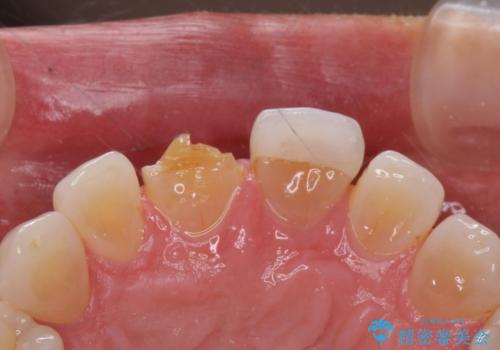

- 前歯につけていたべニアが取れたとのことで来院された患者様です。

より脱離リスクの低いクラウンでの修復を行います。

取れていない方のべニアも周囲の歯と色調が合っていなかったため、一緒にやり替えました。

脱離リスクを抑えつつ、審美性も確保できたことで大変喜んでいただけました。